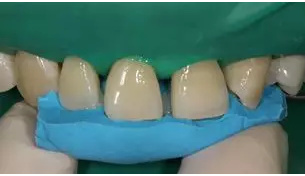

5.牙體微預(yù)備:放置橡皮障,再次確認(rèn)硅橡膠背板就位良好后,11,12,21,23 使用金剛砂車針輕輕打磨一層厚度約 0.1mm,切忌對整個(gè)唇面進(jìn)行打磨。

病例分享|復(fù)合樹脂微創(chuàng)美學(xué)修復(fù)關(guān)閉上前牙間隙

牙體微預(yù)備

8.分層堆塑:硅橡膠背板就位于口內(nèi),使用瓷納美E2 色樹脂進(jìn)行腭側(cè)堆塑,形成厚約為 0.5mm 腭側(cè)釉質(zhì)壁,光照20s,移走硅橡膠背板,腭側(cè)繼續(xù)光照 20s。接著使用 D2 色樹脂進(jìn)行充填,注意充填的厚度約為0.5mm,長度短于切端1~2mm,且頸部的厚度應(yīng)逐步遞減。然后使用 E2色樹脂恢復(fù)唇面及切端,厚度約為1~1.5mm。堆塑時(shí)應(yīng)兩顆牙同時(shí)進(jìn)行,以便及時(shí)調(diào)整牙齒的寬度,堆塑完成后應(yīng)檢查兩牙寬度是否一致,是否協(xié)調(diào)對稱,有無懸突等。

E2樹脂堆塑腭側(cè)釉質(zhì)壁